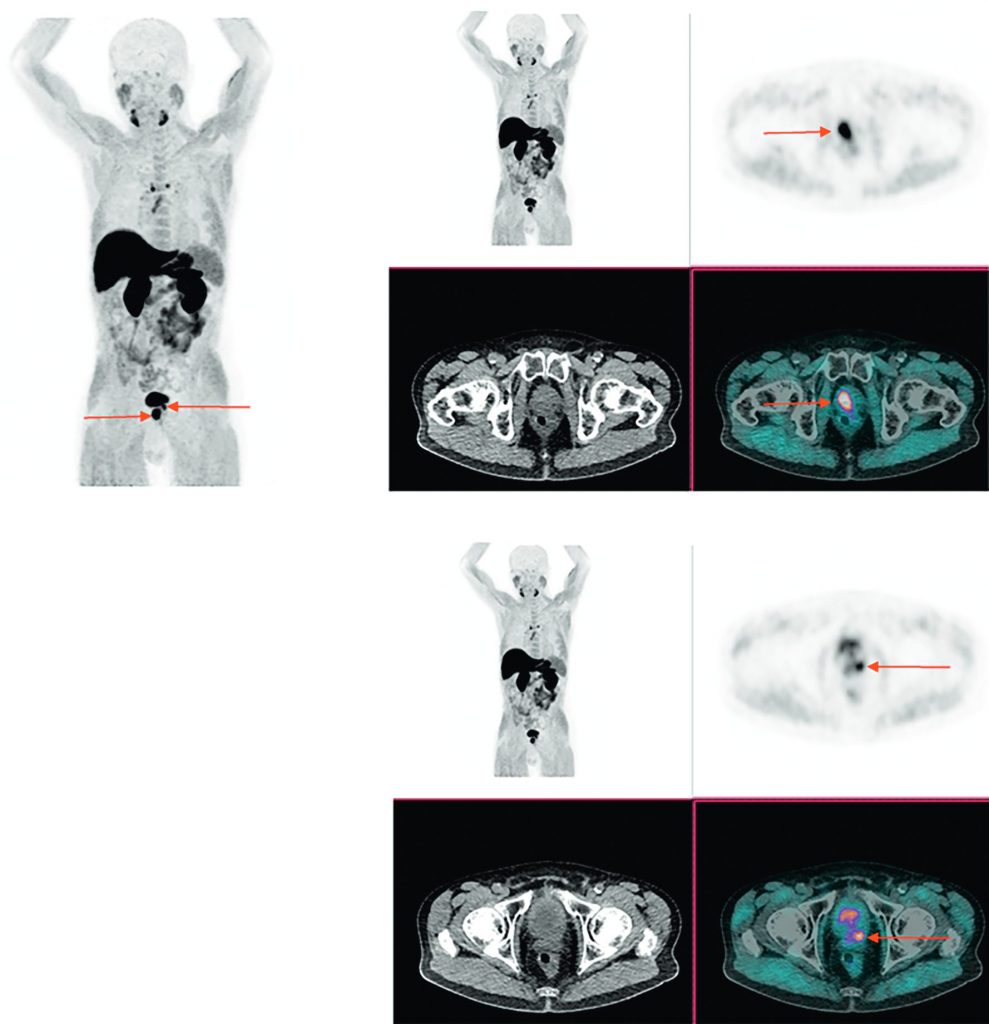

la TEP à la fluorocholine (18FCH), qui peut être proposée pour le bilan d’extension initial des patients à haut risque de récidive et en intention de traitement curatif (figure 30.4).

Fig. 30.4 TEP-TDM à la 18FCH. MIP 3D et coupe axiales TEP, TDM et TEP-TDM centrées sur la prostate.

Bilan d’extension initial d’un patient présentant un adénocarcinome prostatique avec un score de Gleason 4 + 4. Images mettant en évidence un hypermétabolisme des lésions prostatiques bilatérales (flèches rouges), sans hypermétabolisme suspect de lésion secondaire à distance.

Source : CERF, CNEBMN, 2022.

- la TEP-TDM à la 18FCH sera recommandée pour l’exploration des récidives biologiques, plus particulièrement si le taux de PSA ≥ 2 ng/ml et/ou un temps de doublement du PSA ≤ 6 mois (figure 30.5) ;

- la TEP aux analogues de l’antigène membranaire spécifique de la prostate (PSMA) est indiquée chez les patients présentant une récidive biologique lorsque la TEP à la 18FCH est négative (figure 30.6).

Fig. 30.5 TEP-TDM à la F-Choline : bilan d’extension d’une récidive biologique (taux de PSA à 7 ng/ml) d’un adénocarcinome prostatique initialement classé Gleason 4 + 4 et traité par radiothérapie externe.

Images mettant en évidence un hypermétabolisme suspect isolé prostatique gauche (MIP 3D (A), coupe axiale TDM (B) et TEP-TDM (C, flèche rouge), dont les biopsies ciblées ont confirmé une récidive.